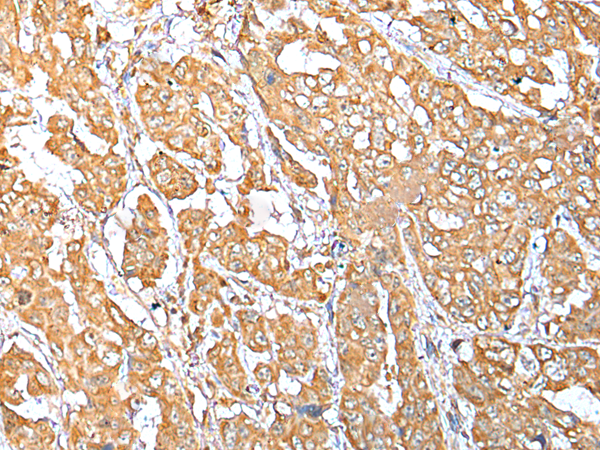

IHC positive control: |

Human breast cancer and human esophagus cancer |